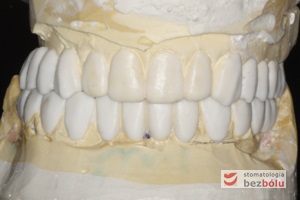

Modele gipsowe z wax-up'em - technik dentystyczny kreuje przyszły kształt zębów za pomocą wosku naniesionego na model

Modele gipsowe z wax-up’em – technik dentystyczny kreuje przyszły kształt zębów za pomocą wosku naniesionego na model